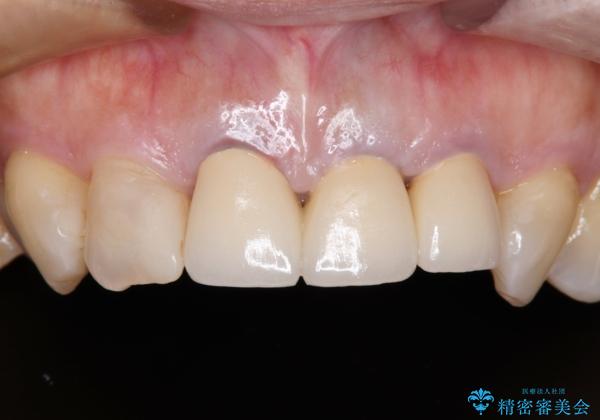

透明感のある自然な色合いとなり、患者様には大変満足していただけました。